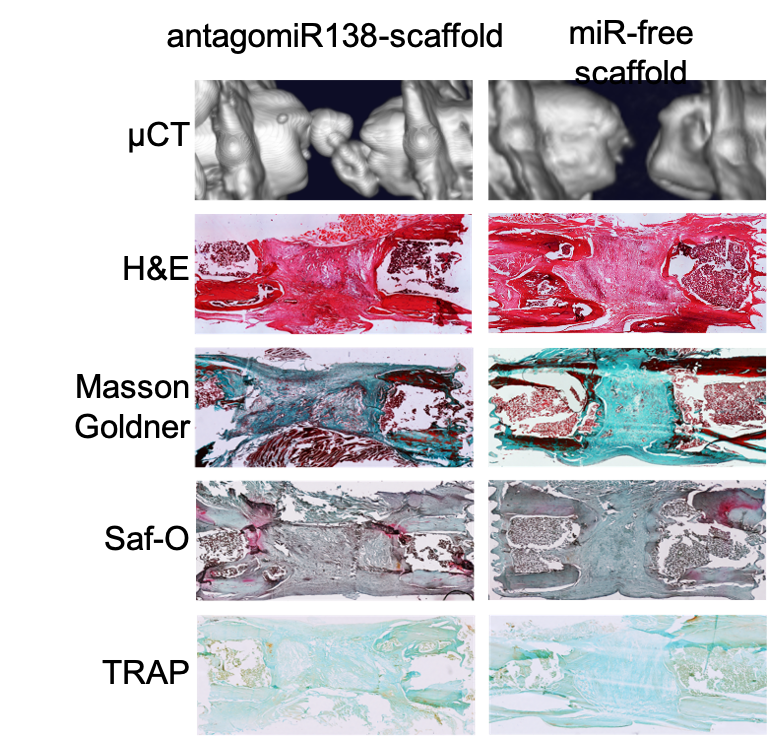

Objective 4: Evaluate in vivo healing and antimicrobial efficacy of the scaffold in a rat infection model. During my fourth objective, I evaluated the regenerative efficacy of the scaffolds containing genetic cargoes using two in vivo models. The miR-26a-activated scaffolds and antagomiR-133a-activated scaffolds were assessed in vivo in a calvarial defect model. The antagomiR-138-activated scaffold was assessed in the femoral defect model. Finally, I incorporated antagomiR-138 into scaffolds containing Cu-BG nanoparticles and assessed their osteogenic and angiogenic potential using the ex ovo chick embryo model.